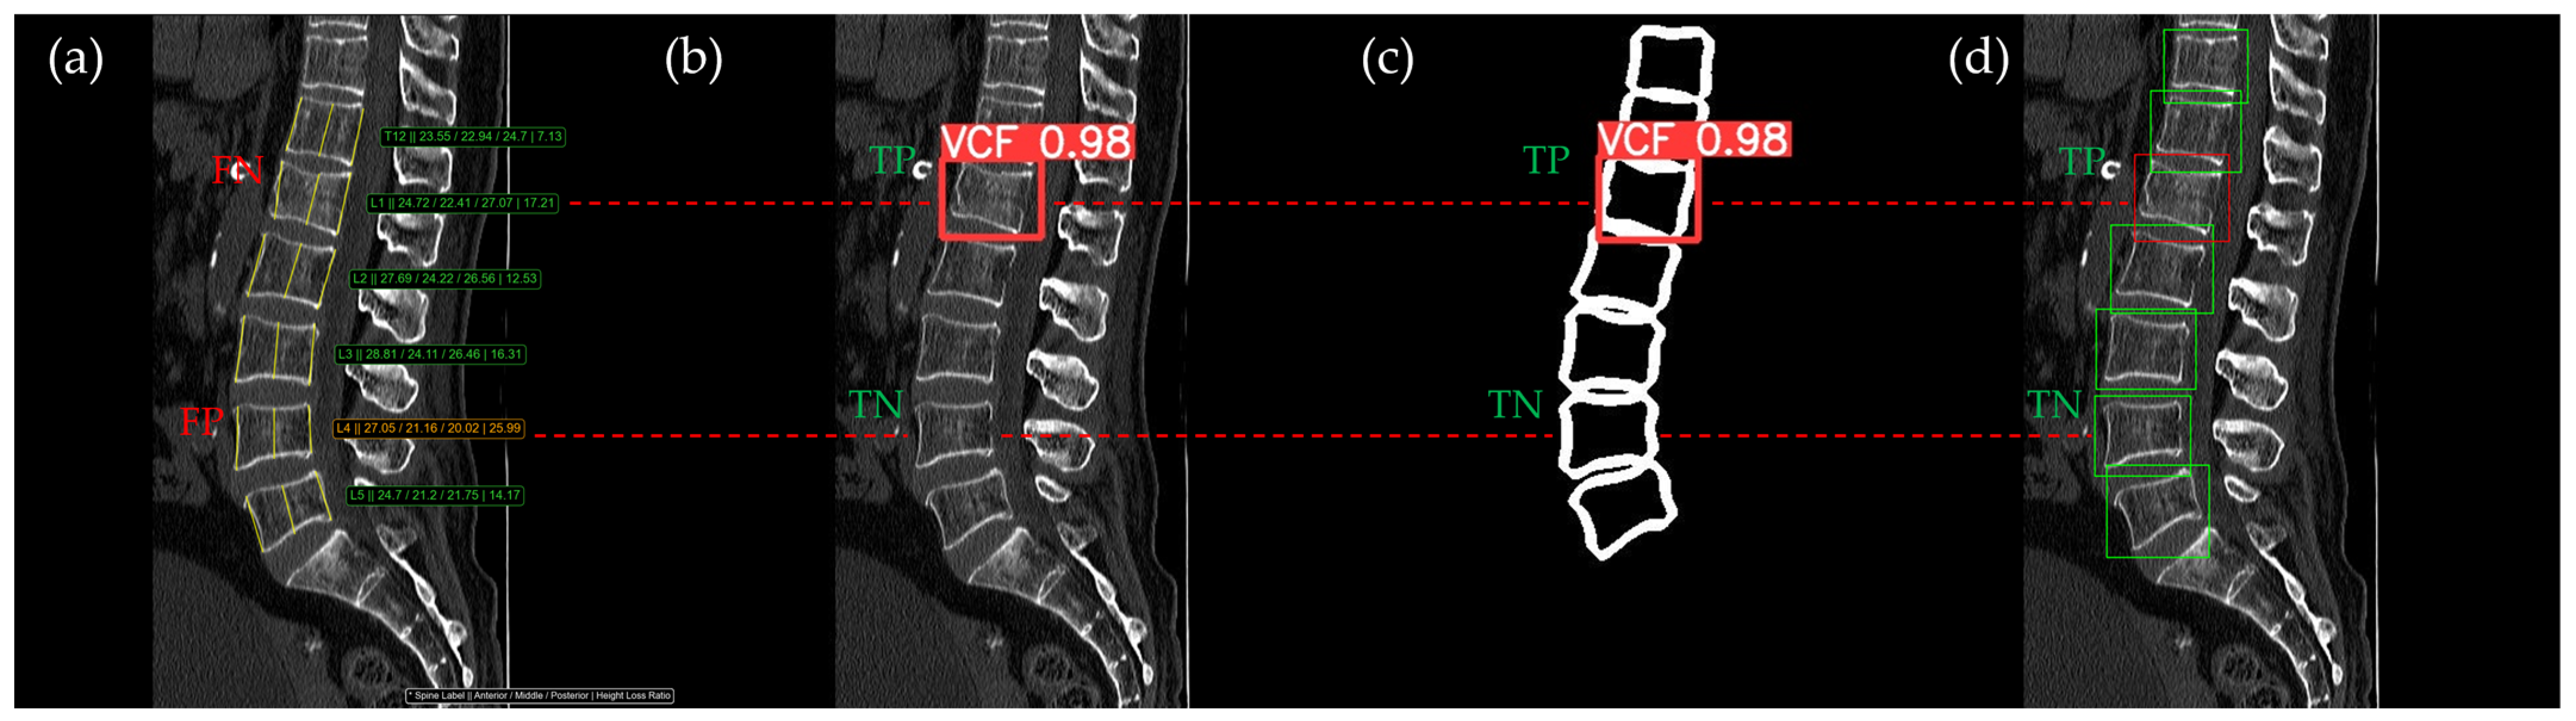

Figure 10, Figure 11, Figure 12, Figure 13 and Figure 14 illustrate typical examples of results for HLR, EEVD, TSVD_SD, and TSVD_DC in patients with acute VCFs. The results of applying different methodologies to the same patient image and identical slice locations were as follows. In the HLR results, each vertebra was marked with yellow solid lines indicating the height measurement lines for the anterior, middle, and posterior regions. The measured height values and HLR percentages were displayed on the right side of the image. If the HLR percentage ranged between 25% and 40%, it was highlighted in orange, while values of 40% or higher were highlighted in red. In the EEVD results, the VCF detection outputs were displayed along with their respective confidence scores based on the input patient images. For the TSVD_SD results, after performing spine segmentation, the model extracted only the spine contour, and the VCF detection results with their corresponding confidence scores were presented. In the TSVD_DC results, bounding boxes were generated for each vertebral body, with normal vertebrae represented in green and vertebrae identified as VCFs displayed in red.

Figure 12.

The VCF detection results from four different methods. (a) HLR, (b) EEVD, (c) TSVD_SD, and (d) TSVD_DC. The acute VCF, as confirmed by the radiologist, was located at the L1 level. TP, TN, FP, and FN were marked at the same level with a red dotted line.

In Figure 12, the L1 vertebra was identified as having an acute VCF, while L4 was determined to be normal. At L1, there was cortical breakage and step-off at the anterior lower region. The HLR method failed to detect this VCF, while EEVD, TSVD_SD, and TSVD_DC successfully identified it. In the HLR assessment, L4 exhibited physiological wedging, with the posterior height measuring more than 25% lower than the anterior and middle heights. Due to the S-shaped curvature of the human spine, it is common for the posterior height to be slightly lower in the L4–L5 region. Consequently, EEVD, TSVD_SD, and TSVD_DC did not classify L4 as a VCF (TN).